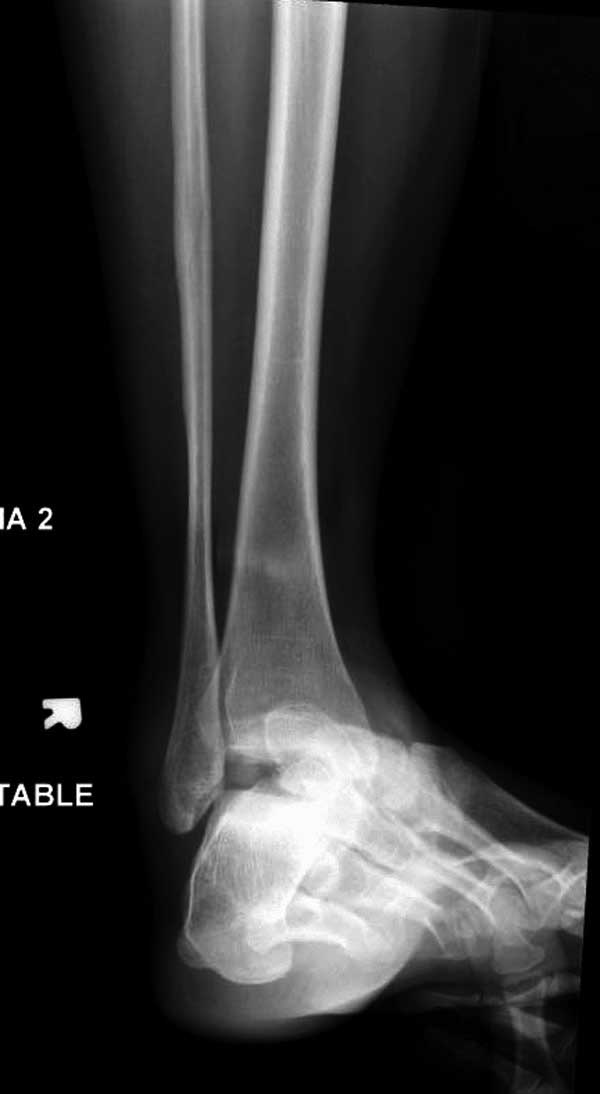

Женщина 28 лет, политравма.

По протоколу обследования больных с травмой сделаны все исследования и выставлен диагноз: разрыв печени и селезенки; множественные переломы ребер и лицевого черепа; стабильный перелом позвоночника, переломо-вывих головки левого бедра, перелом диафиза правого бедра, переломо-вывих правого тарана.